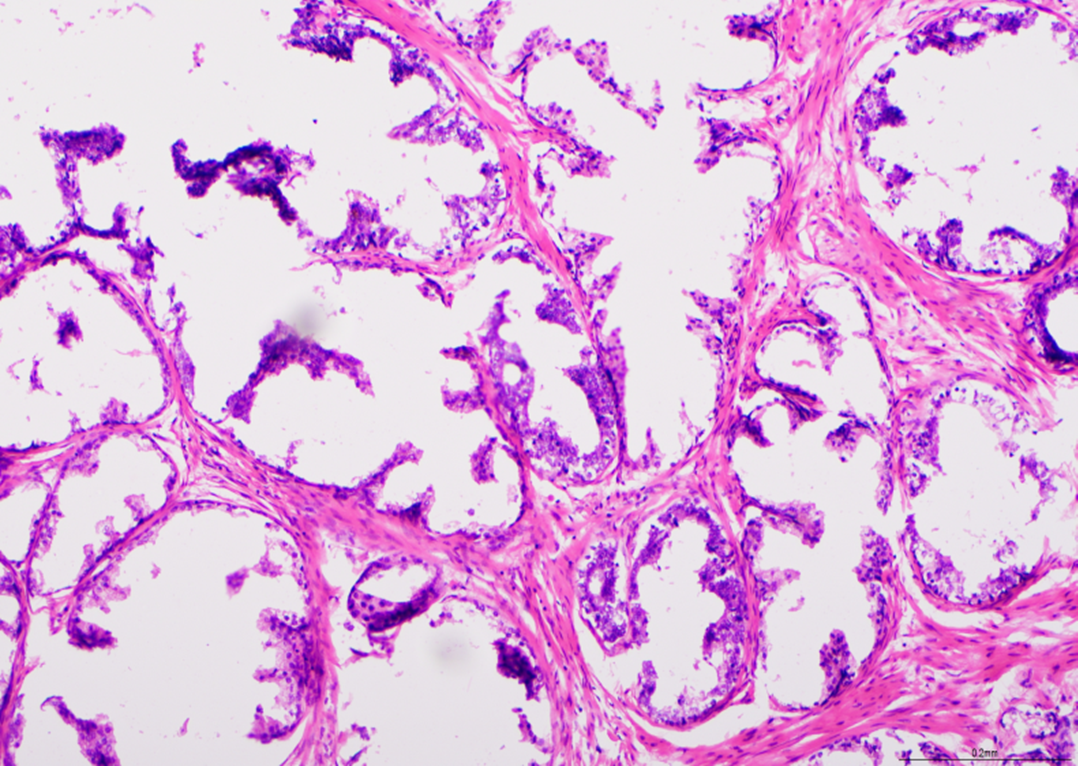

H E - shema BMT-a

Vidljivo pri 20-kratnom uvećanju. Sveukupno vrlo dobra priprema, ali su bodovi oduzeti zbog nabora i pregiba, gubitka materijala i pozadinskog bojenja hematoksilinom. Ovaj preparat je dobio ocjenu 8/10.